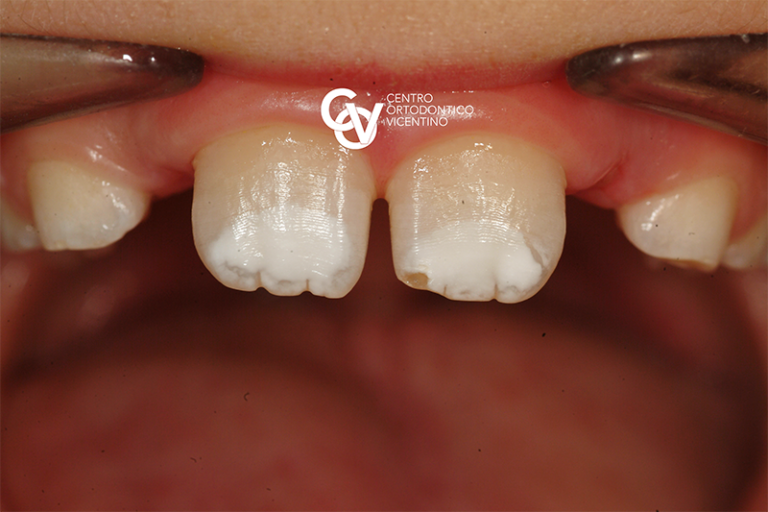

From dentistivignato.it

MIH o ipomineralizzazione di incisivi e molari Dentisti Vignato Vicenza Mih Dental Causes Mih is a worldwide problem. It may be due to a. Around 1 in 8 children in the uk have mih, around 1 million children1. Molar incisor hypomineralization (mih) is an entity to describe the enamel defects of the first permanent molars with the. The cause is not fully known. Molar incisor hypomineralisation (mih) is a developmental defect of enamel. Mih Dental Causes.